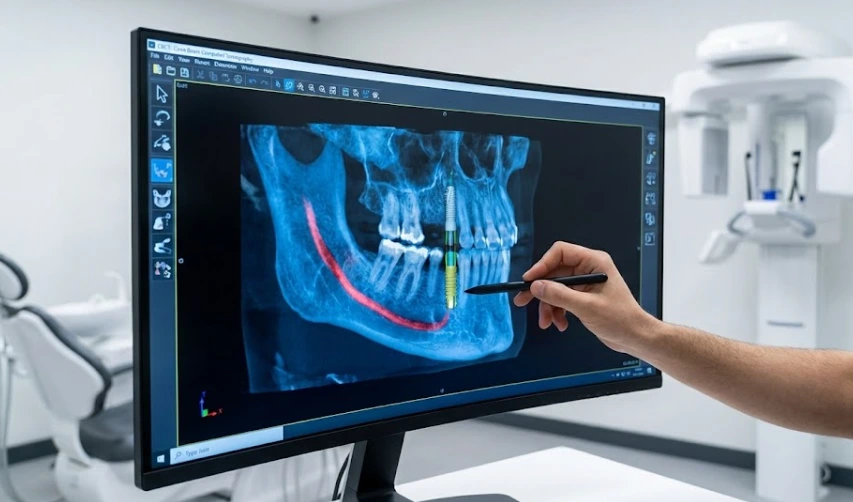

3D X-rays maximizează precizia implanturilor.

Tomografia computerizată cu fascicul conic (CBCT), în acest caz, este tehnologia care schimbă situația. Oferă o imagine de 360 de grade, de înaltă rezoluție a anatomiei pacientului. Dar trebuie să luăm în considerare de ce această „privire” specifică este crucială pentru sănătatea și longevitatea dumneavoastră generală.

Maxilarul dumneavoastră nu este doar un os; este o rețea complexă de nervi și sinusuri. De exemplu, nervul alveolar inferior furnizează senzație buzei inferioare și bărbiei. Într-un scanare 2D, acest nerv poate fi reprezentat ca fiind mai departe de locul implantului decât este în realitate. Mulțumită tehnologiei 3D, dentistul Polen Akkılıç și echipa sa pot cartografia precis traseele nervilor până la ultimul zecimal de milimetru, evitând astfel ca pistonul de implant de titan să interfereze cu aceste zone geografic sensibile.

În maxilarul superior, sinusul maxilar este unul dintre mai multe cavități foarte delicate, căptușite cu o membrane subțire ca o coajă de ou. Dacă osul este prea subțire, implantul ar putea penetra accidental această cavitate. Astfel, imaginile 3D ne indică volumul exact de os pe care îl avem, și împreună cu informațiile despre dacă avem sau nu suficient spațiu pentru implant, ne permit să decidem dacă trebuie să realizăm un „ridicare de sinus” înainte de procedură la clinica noastră din Istanbul.

Așadar, la ce folosesc toate aceste scanări 3D? La Lema Dental Clinic, nu doar privim scanarea, ci o folosim pentru a crea un „ghid chirurgical”. Acesta este un șablon 3D-tipărit, personalizat pentru dinte și plasat în timpul intervenției.

Realitatea este că acest ghid este un GPS pentru mâna chirurgului. Restricționează burghiul la un unghi și o adâncime exact planificate, conform software-ului nostru digital. Astfel, greșelile umane sunt eliminate, timpul petrecut de pacient în sala de operație este redus și, cel mai important, umflarea post-operatorie este minimizată, deoarece „punctul de intrare” este mai mic și mai precis.